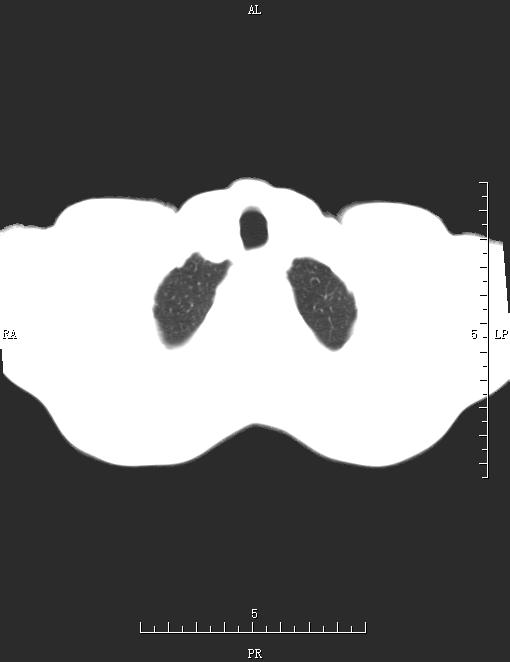

CT51973:胸部CT

男,54岁,胸部不适3天。

双侧肺门及纵隔多发淋巴结肿大,左侧肺门似增大,双肺内见淋巴管炎,左上肺多发小结节,右侧胸腔积液,心包少量积液,腹腔少量积液。另:肝右上叶不规则低密度影。综合考虑:恶性转移。建议增强,查找原发灶。

两肺内可见多发斑点结节索条影,双侧肺门及纵隔内见多发肿大淋巴结,右侧胸腔积液,肝周少许液体密度影,肝内见多发低密度影,考虑:肺结节病可能性大。肝内多发性结节,肝转移?